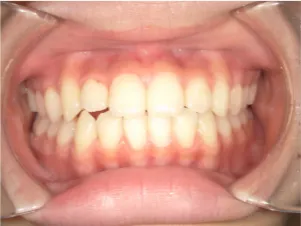

治療後⑩高2:17y7m 抜歯治療終了

口元の治療前後:15y5m→17y7m スッキリしました